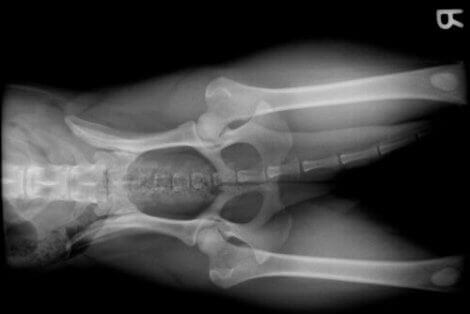

- Rasen. Visse hunderaser, som schæfer, utvikler vanligvis hoftedysplasi. På den annen side har raser som golden retriever, rottweiler eller doberman, på grunn av sin store størrelse og raske vekst, en tendens til å lide av dysplasi i skulder eller albue.

- Frakturer som involverer et ledd.

- Fremre korsbåndskade. På grunn av overanstrengelse, overdreven trening eller en liten rasetype, kan det fremre korsbåndet ryke. Dette vil føre til alvorlige leddproblemer.